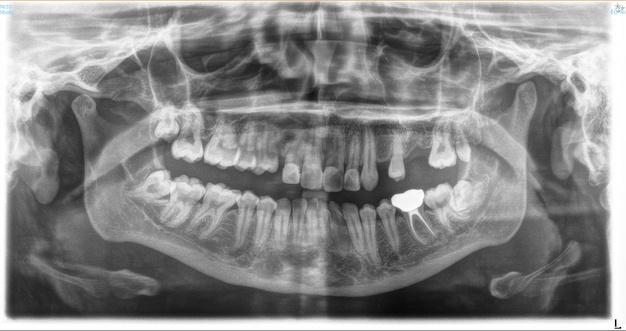

ฟนและกระดกขากรรไกรมหลายสวนทซอนอยใตเหงอก และเมอ เกดความผดปกตขนอาจจะไมสามารถมองเหนไดเพยงจากการ

การสงถายภาพรงส เพอการวนจฉยโรคในชองปากมความสาคญอยางยง

โดยเฉพาะในการประเมนรอยผของฟน ในผปวยทไมเคย ตรวจสขภาพชองปากมากอนหรอผทมาพบทนตแพทย เป นครงแรก

นอกเหนอจากการตรวจรอยผในชองปากจากการตรวจด

โดยตรงแลว ทนตแพทยจะพจารณาการถายภาพรงสใน

ชองปาก เพอชวยตรวจหาบรเวณรอยผดานประชดฟน (proximal caries)